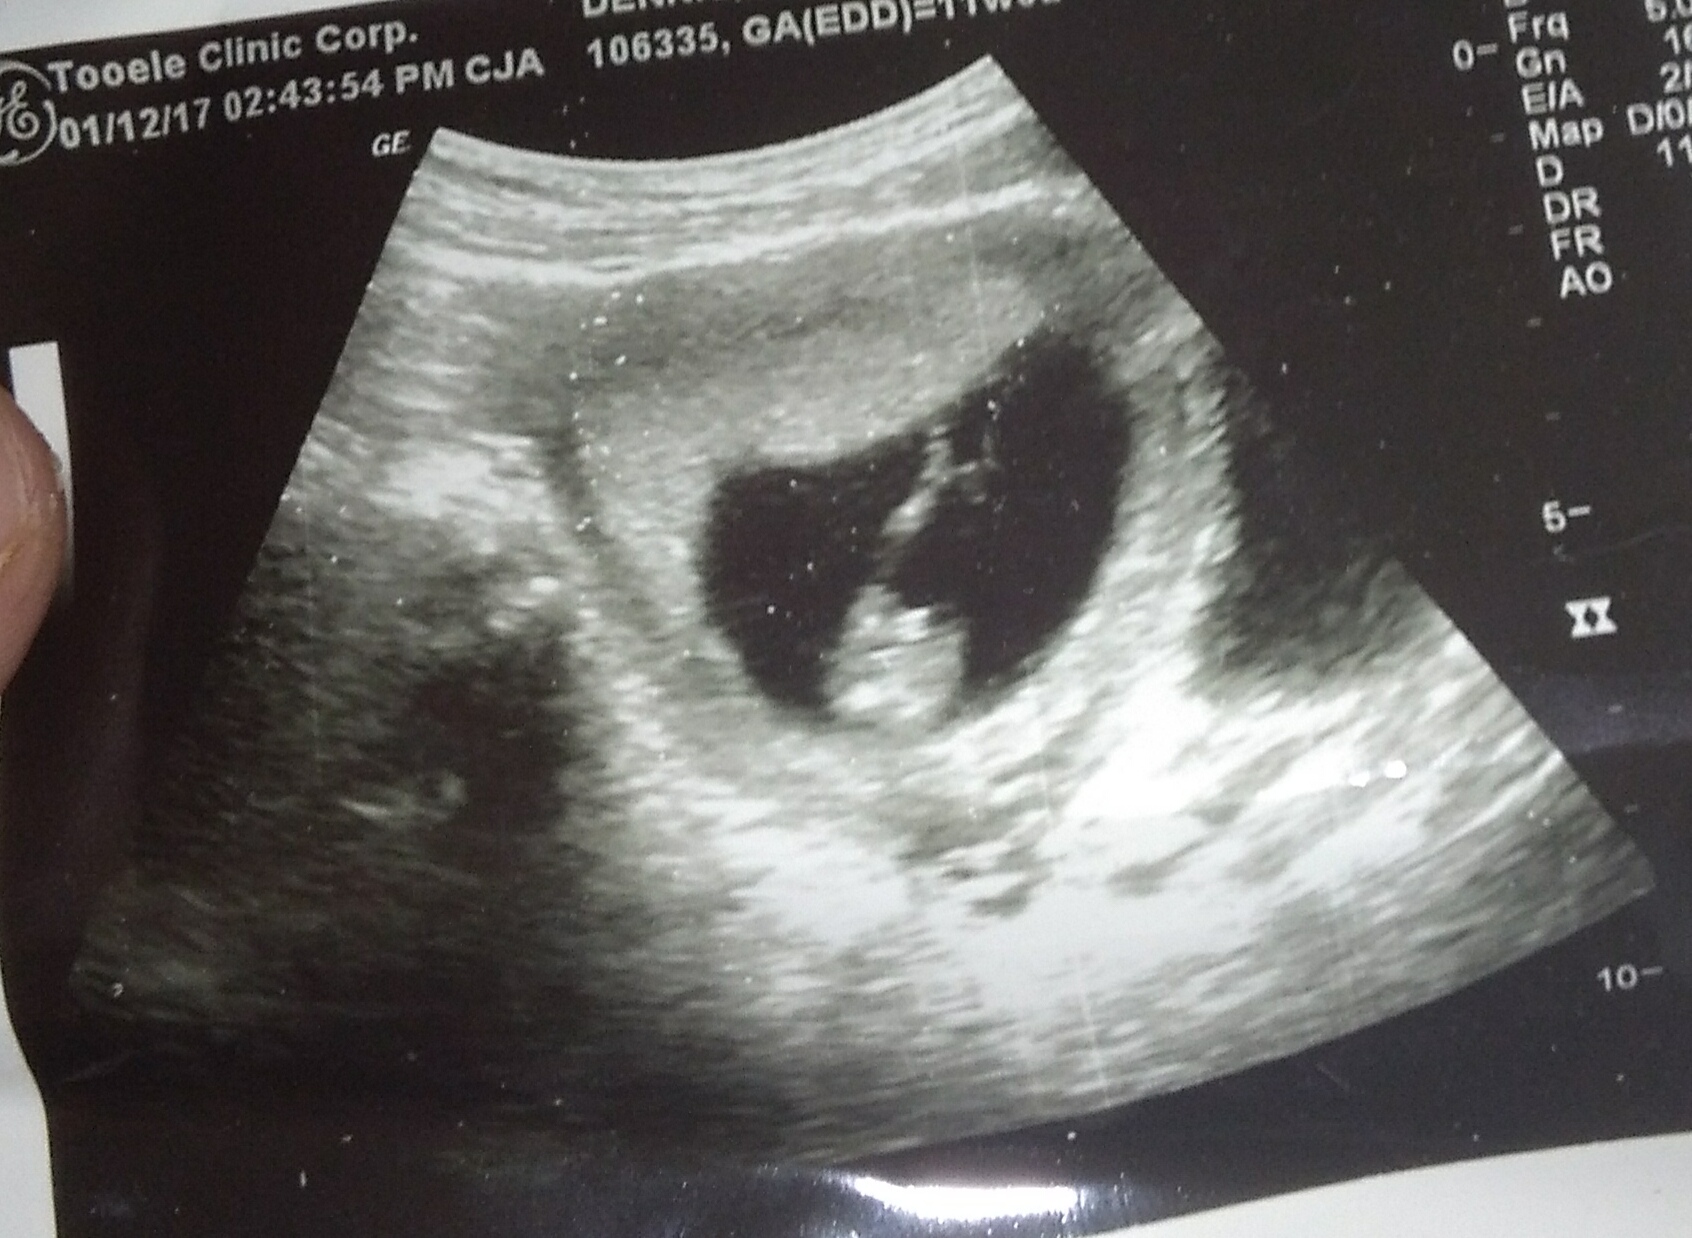

How Do They Date A Pregnancy Scan - Does an Ectopic Pregnancy Show on Test? | New Health Advisor / Accurately date your pregnancy by measuring your baby.. This is referred to as a. The 2d image from the scan allows the sonographer to see your baby and work out baby's gestational age and when they're due, so you'll be given an idea of baby's due date which is why it is often called a dating scan! Early scans are not offered to work out your due date and even if you've had a. It's at this time that you will be told how many weeks pregnant you are. The anatomy scan is a level 2 ultrasound, which is typically performed between 18 and 22 weeks.

The point of the scan is to work out how many weeks pregnant you are. Also known as an anomaly scan or anatomic survey, an anatomy scan is the most extensive ultrasound exam carried out on the fetus during pregnancy. It checks if your baby is at the right place or not, it finds the accurate due date, determines the reason for any spotting or. The 2d scan is an external transabdominal scan. At 6 weeks they can be upto 5 days out.

11 Weeks 6 Days, boy or girl based on pictures? from www.genderdreaming.com This is referred to as a. If your periods are irregular or you do not remember your last period, you should wait for your first ultrasound pregnancy scan. #8 littleblonde, feb 1, 2010. Ultrasound scans have been used in pregnancy for decades, and there's no evidence that they're harmful if carried out correctly (bmus nd, nhs 2018a, ranzcog 2018b). It's used to see how far along in your pregnancy you are and check your baby's development. At 6 weeks they can be upto 5 days out. We calculate your expected due date by comparing the first day of your last menstrual period with specific measurements of the foetus by measuring the distance from the top of the head (crown) to the bottom of the body (rump). This scan is to calculate how far along in your pregnancy you are and to determine an estimated due date for your baby's arrival.

Although you don't need a scan to confirm your pregnancy, the dating, and viability ultrasound scan help in many other aspects.

Find out why a blood screening test was abnormal. An nt scan cannot diagnose down syndrome or any other chromosome. #8 littleblonde, feb 1, 2010. Early scans are not offered to work out your due date and even if you've had a. The anatomy scan, which is carried out around 20 weeks, examines your baby's anatomy in great detail. Gestational age is the age of your baby calculated from the date of your last menstrual period. What is the dating scan for? It's used to see how far along in your pregnancy you are and check your baby's development. This scan should hopefully confirm that your baby's body is forming correctly. The nuchal translucency scan is performed when the fetus is between 77 to 97 days old (i.e. Ultrasound scans have been used in pregnancy for decades, and there's no evidence that they're harmful if carried out correctly (bmus nd, nhs 2018a, ranzcog 2018b). It is performed between weeks 18 and 22 and is the one most people are referring to when they talk about their routine pregnancy scan or their 20 week scan. 'is a scan that uses sound waves to create a picture.

I went up 5 days from my scan i had at 6 weeks to the scan i had at 12 weeks. Of course you have probably already used an online due date calculator. Thus, scanning later in the pregnancy beyond the date of normal foetal resorption would give a better indication of numbers, were it not for the fact that the puppies nearest to the probe head are likely to obscure those behind. The dating scan can include a nuchal translucency (nt) scan, which is part of the combined screening test for down's syndrome, if you choose to have this screening. Also known as an anomaly scan or anatomic survey, an anatomy scan is the most extensive ultrasound exam carried out on the fetus during pregnancy. The 2d scan is an external transabdominal scan. How much do private early pregnancy scans cost? The nt scan is part of the combined screening test for down syndrome , but your sonographer will also take measurements to confirm your due date. So, before you book your scan, ask what experience the sonographers have and whether they're able to perform vaginal scans if that is required. The dating scan, also known as the 12 week scan, is offered between 8 and 14 weeks and it will give you an accurate due date. Early scans are not offered to work out your due date and even if you've had a. Gestational age is the age of your baby calculated from the date of your last menstrual period. At 6 weeks they can be upto 5 days out.

The 2d image from the scan allows the sonographer to see your baby and work out baby's gestational age and when they're due, so you'll be given an idea of baby's due date which is why it is often called a dating scan! The costs of these scans really varies. This scan is to calculate how far along in your pregnancy you are and to determine an estimated due date for your baby's arrival. I went up 5 days from my scan i had at 6 weeks to the scan i had at 12 weeks. At 6 weeks they can be upto 5 days out. The point of the scan is to work out how many weeks pregnant you are. You may be offered an early pregnancy scan if you are experiencing bleeding and spotting in the early stages of pregnancy. It is recommended to have your first pregnancy ultrasound scan between 6 to 9 weeks. Of course you have probably already used an online due date calculator. It's at this time that you will be told how many weeks pregnant you are. The 2d scan is an external transabdominal scan. If you choose to have a dating scan, it will most probably be your first scan. They can then enter your age or date of birth in a computer program to calculate the risk of your baby having an abnormality.